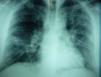

A 39-year-old man (heavy smoker, hypertensive and moderately obese) presented at the Internal Care Unit in October 2012 suffering from a 3-day history of dyspnea, paroxysmal productive cough and retrosternal pain, with no fever. Scarce end-expiratory crackles in middle and lower lung fields bilaterally with associated mildly prolonged expiratory phase of respiration and mild leucocytosis were recorded. The patient refused hospitalization, and two days later he returned due to worsened, intense dyspnea at rest, heart rate of 130/min and fever (38.5°C). A new chest X-ray revealed more intense alveolar infiltrates, diffuse and expanded throughout the whole left lung and the right middle lung field (Fig. 1). Routine blood tests showed leukocytosis, elevated neutrophiles and monocytes, relatively increased CRP (7.5mg/dl), ESR (73mm/h), ALT (83U/L) and LDH (484U/L).